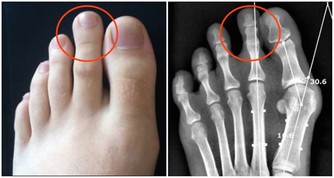

缺乏維生素B2的人容易得A症?

流行病學認為A症具有遺傳性,這其實是個錯誤的結論。真正的原因是,父母與子女在飲食結構上具有高度相似性,父母愛吃辣的,經常上火,處於缺乏維生素B2的狀態,那麼子女也必定愛吃辣的,也會缺乏維生素B2,即使子女以後與父母分開了,他(她)的飲食習慣也會保留下來,所以,與父母得相同的病就不足為奇了。

為什麼常吃五穀雜糧的人不易得A症呢?

現在你應該明白了吧,其實是五穀雜糧中(主要在皮、殼上)所含的維生素B2起了作用,如果把皮和殼都去除了,效果就會大打折扣。有些人常吃複合維生素,認為自己不會缺乏維生素B2,實際上,複合維生素中所含的B2遠遠不能滿足人的日常需求,必須單獨補充維生素B2。